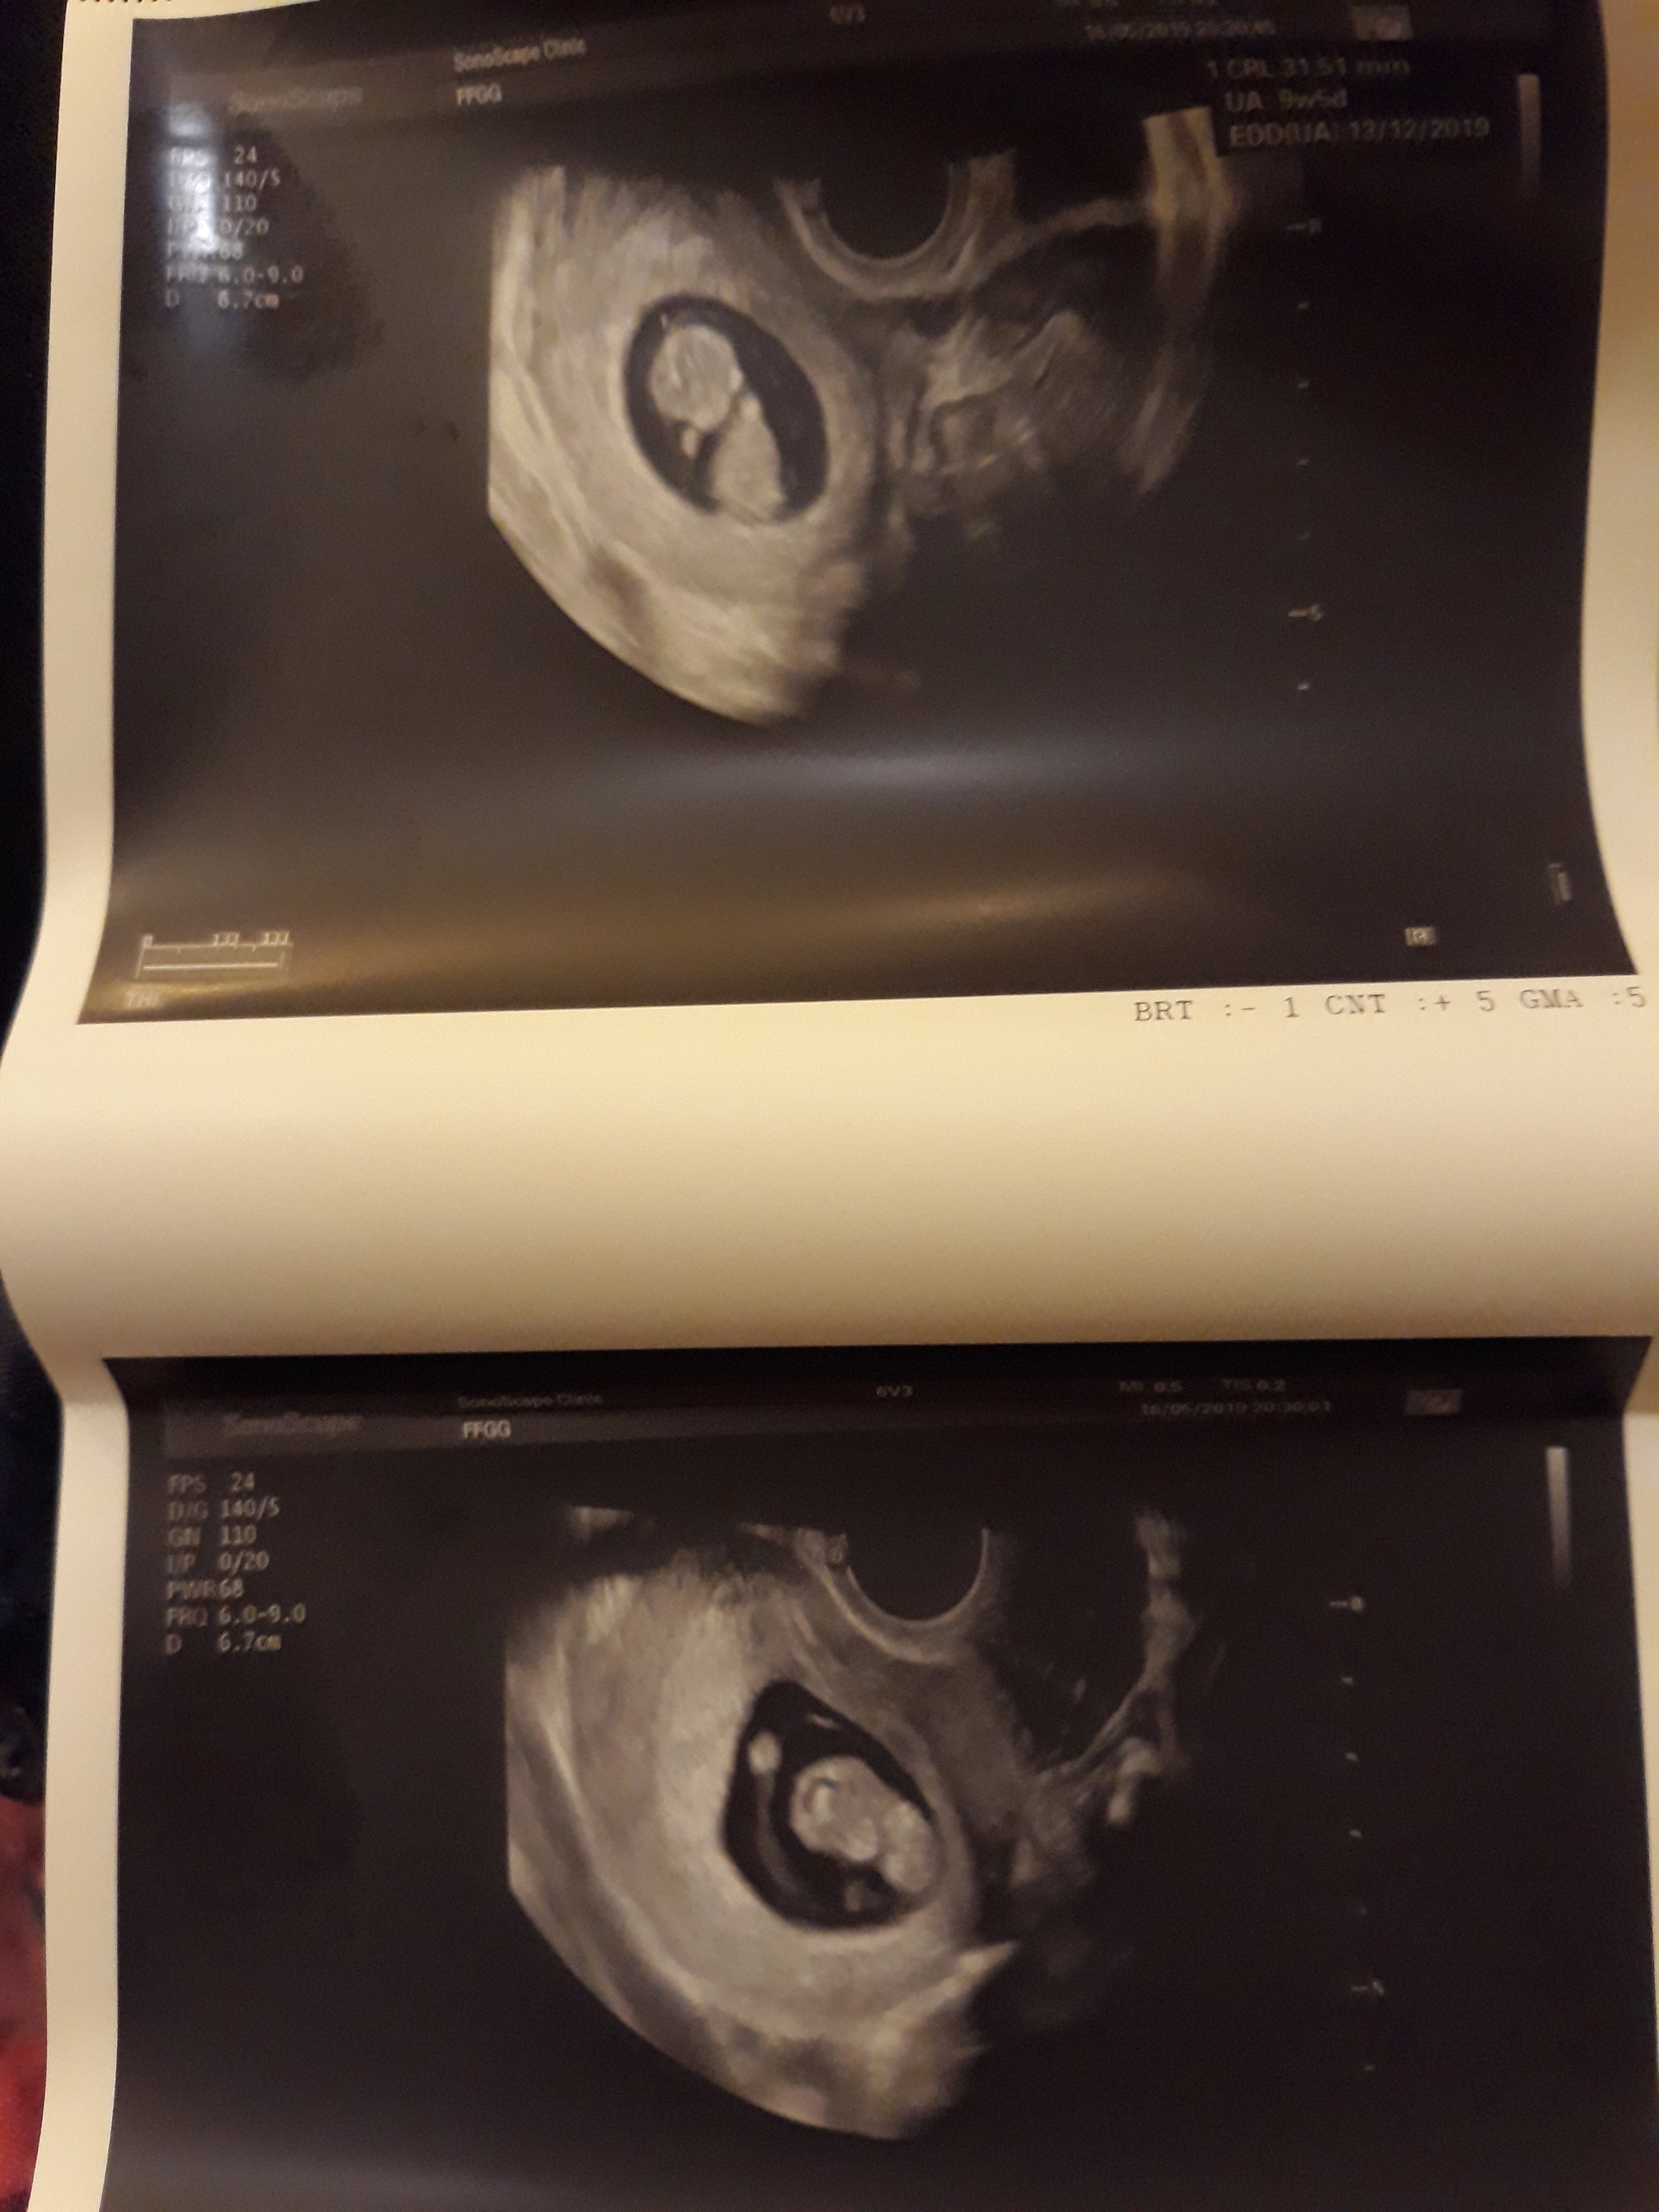

Jesteśmy po usg mamy już 27 mm i serduszko bije z prędkością 174 na minutę słyszeliśmy dziś z partnerem pierwszy raz serduszko

Super gratuluję [emoji4]ktory tydzień?? [emoji173]Jesteśmy po usg mamy już 27 mm i serduszko bije z prędkością 174 na minutę słyszeliśmy dziś z partnerem pierwszy raz serduszkoZobacz załącznik 973575

Z usg 9 tydzień dzień 2 a z Om 10 tydzień i termin na 17 grudniaSuper gratuluję [emoji4]ktory tydzień?? [emoji173]